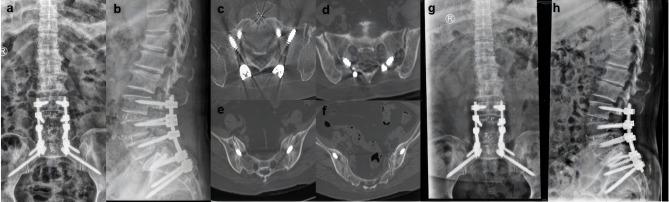

Between January 2018 and June 2022, 7 patients underwent salvage surgery with the CBT screw fixation technique assisted by the Mazor Renaissance robot system in our institution. Intraoperative observations were recorded for blood loss, duration of operation, and fluoroscopy time. Complications related to CBT screws were also recorded. The accuracy of CBT screws was recorded in accordance with the modified Gertzbein-Robbins classification. The JOA (Japanese Orthopedic Association) score for low back pain was used to evaluate surgical outcomes.

RESULTS

A total of 26 CBT screws were placed in 7 patients, including 4 females and 3 males. Three patients underwent ASD (adjacent segment disease) and four patients underwent lumbar union failure with loose or compromised PSs (pedicle screws). The mean operation time was 129.29 ± 32.97 minutes, the mean blood loss was 180 ± 52.60 mL, and the mean intraoperative fluoroscopy time was 14.29 ± 3.15 s. All screws were clinically acceptable according to the Gertzbein-Robbins classification. There were no complications related to CBT screws in any of the cases. The JOA scores for low back pain of all patients were significantly improved at the final follow-up.